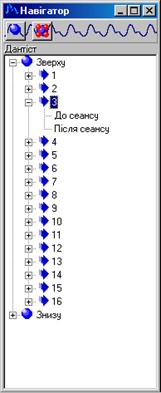

Після реєстрації з^явиться вікно "Навігатор" в якому активні елементи розміщенні по групам. Так навігатор для вертебродіагностики представлений на рисунку 8.2. Можливим є створення структур для навігатора довільної форми (різне число секцій й підсекцій) [17, 18].

Переміщення по навігатору відбувається з допомогою клавіатури або маніпулятора "миша". Після вибору певного елемента 3-го рівня навігатора ("До сеансу" або "Після сеансу") можна приступати до зняття ФПГ даних.